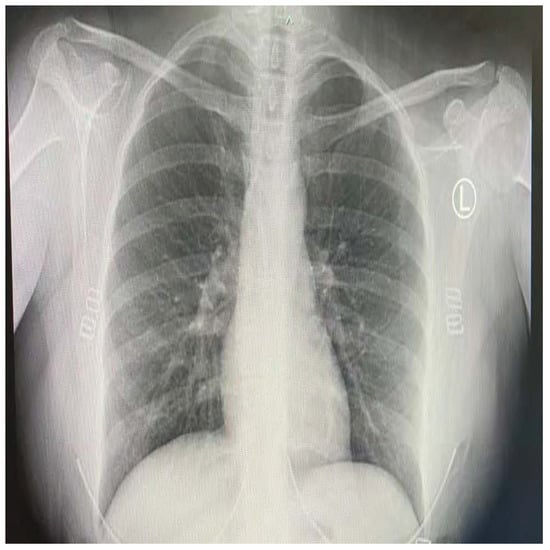

COVID-19 patients who have clinical symptoms are more likely to show abnormal CXR [9]. The main findings of recent studies suggest that these lung images display patchy or diffuse reticular–nodular opacities and consolidation, with basal, peripheral, and bilateral predominance [10]. For example, Figure 1 shows the CXR of a mild case of lung tissue involvement with right infrahilar reticular–nodular opacity. Moreover, Figure 2 shows the CXR of a moderate to severe case of lung tissue involvement. This CXR shows right lower zone lung consolidation and diffuse bilateral airspace reticular–nodular opacities, which are more prominent on peripheral parts of lower zones. Similarly, Figure 3 shows the CXR of a severe case of lung tissue involvement. This is caused by diffuse bilateral airspace reticular–nodular opacities that are more prominent on peripheral parts of the lower zones, and ground glass opacity in both lungs predominant in mid-zones and lower zones. On the other hand, Figure 4 shows an unremarkable CXR with clear lungs and acute costophrenic angles (i.e., normal).

Figure 3.

CXR of COVID-19 subject showing severe lung tissue involvement.